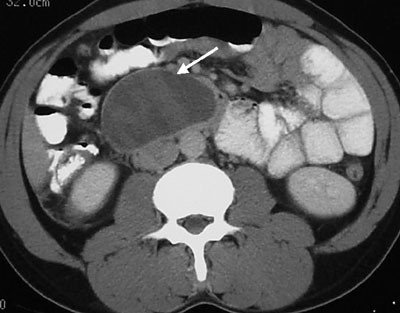

- Kontrastlı KT və ya MRT standart müayinədir, şişi və yayılma dərəcəsini müəyyənləşdirilməsində önəmlidir.

- Görüntüləmdə: erkən arterial fazada contrast tutan və venoz fazada yuyulan, MRT-də hipointens, ətraf toxumalara invaziv, böyüməyə meylli, baş nahiyyəsində yerləşərək xoledoxu və pankreatik axacağı genişləndirən (“iki axacaq simptomu”) törəmə

Mərhələnin təyini

Mərhələnin və rezektabelliyin təyini üçün ilk olaraq KT angioqrafiya və endoskopik USM, sonra diaqnostik laparoskopiya edilir və gərəkərsə, PET istifadə edilir. Mərhələni müəyyənləşdirmək üçün TNM klassifikasiyasına, cərrahi rezektabelliyin təyini üçün metastaz və yerli yayılmalara istinad edilir. Cərrahi rezekstabellik nöqteyi nəzərdən pancreas adenokarsinomasının aşağıdakı formaları ayrıd edilir: